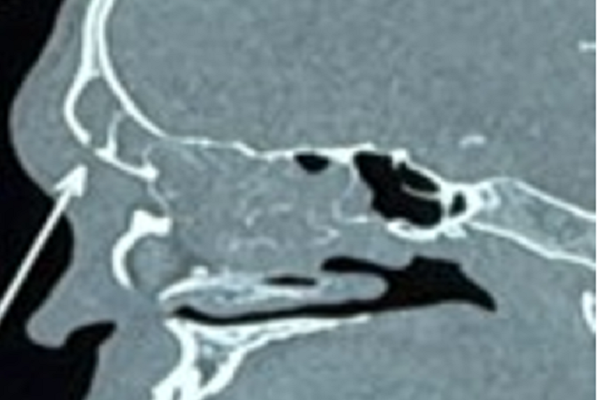

Kết quả chụp CT scan mũi xoang ghi nhận viêm đa xoang và vùng hủy xương thành trước xoang trán phải

Kết quả nội soi mũi ghi nhận nhiều dịch mủ đục chảy từ khe giữa bên phải, niêm mạc phù nề nặng. Chụp CT xoang sau đó đã đưa ra chẩn đoán mang tính quyết định.

Hình ảnh cho thấy tình trạng viêm đa xoang nghiêm trọng, đặc biệt là xoang trán bên phải bị tổn thương nặng. Đáng lo ngại, lớp xương thành trước xoang trán đã bị phá hủy, tạo điều kiện cho ổ mủ lan ra phần mềm vùng trán.

Đây là dấu hiệu điển hình của Pott's Puffy Tumor — một dạng viêm tủy xương trán kèm áp xe dưới màng xương, có thể lan vào nội sọ nếu không được xử lý kịp thời.